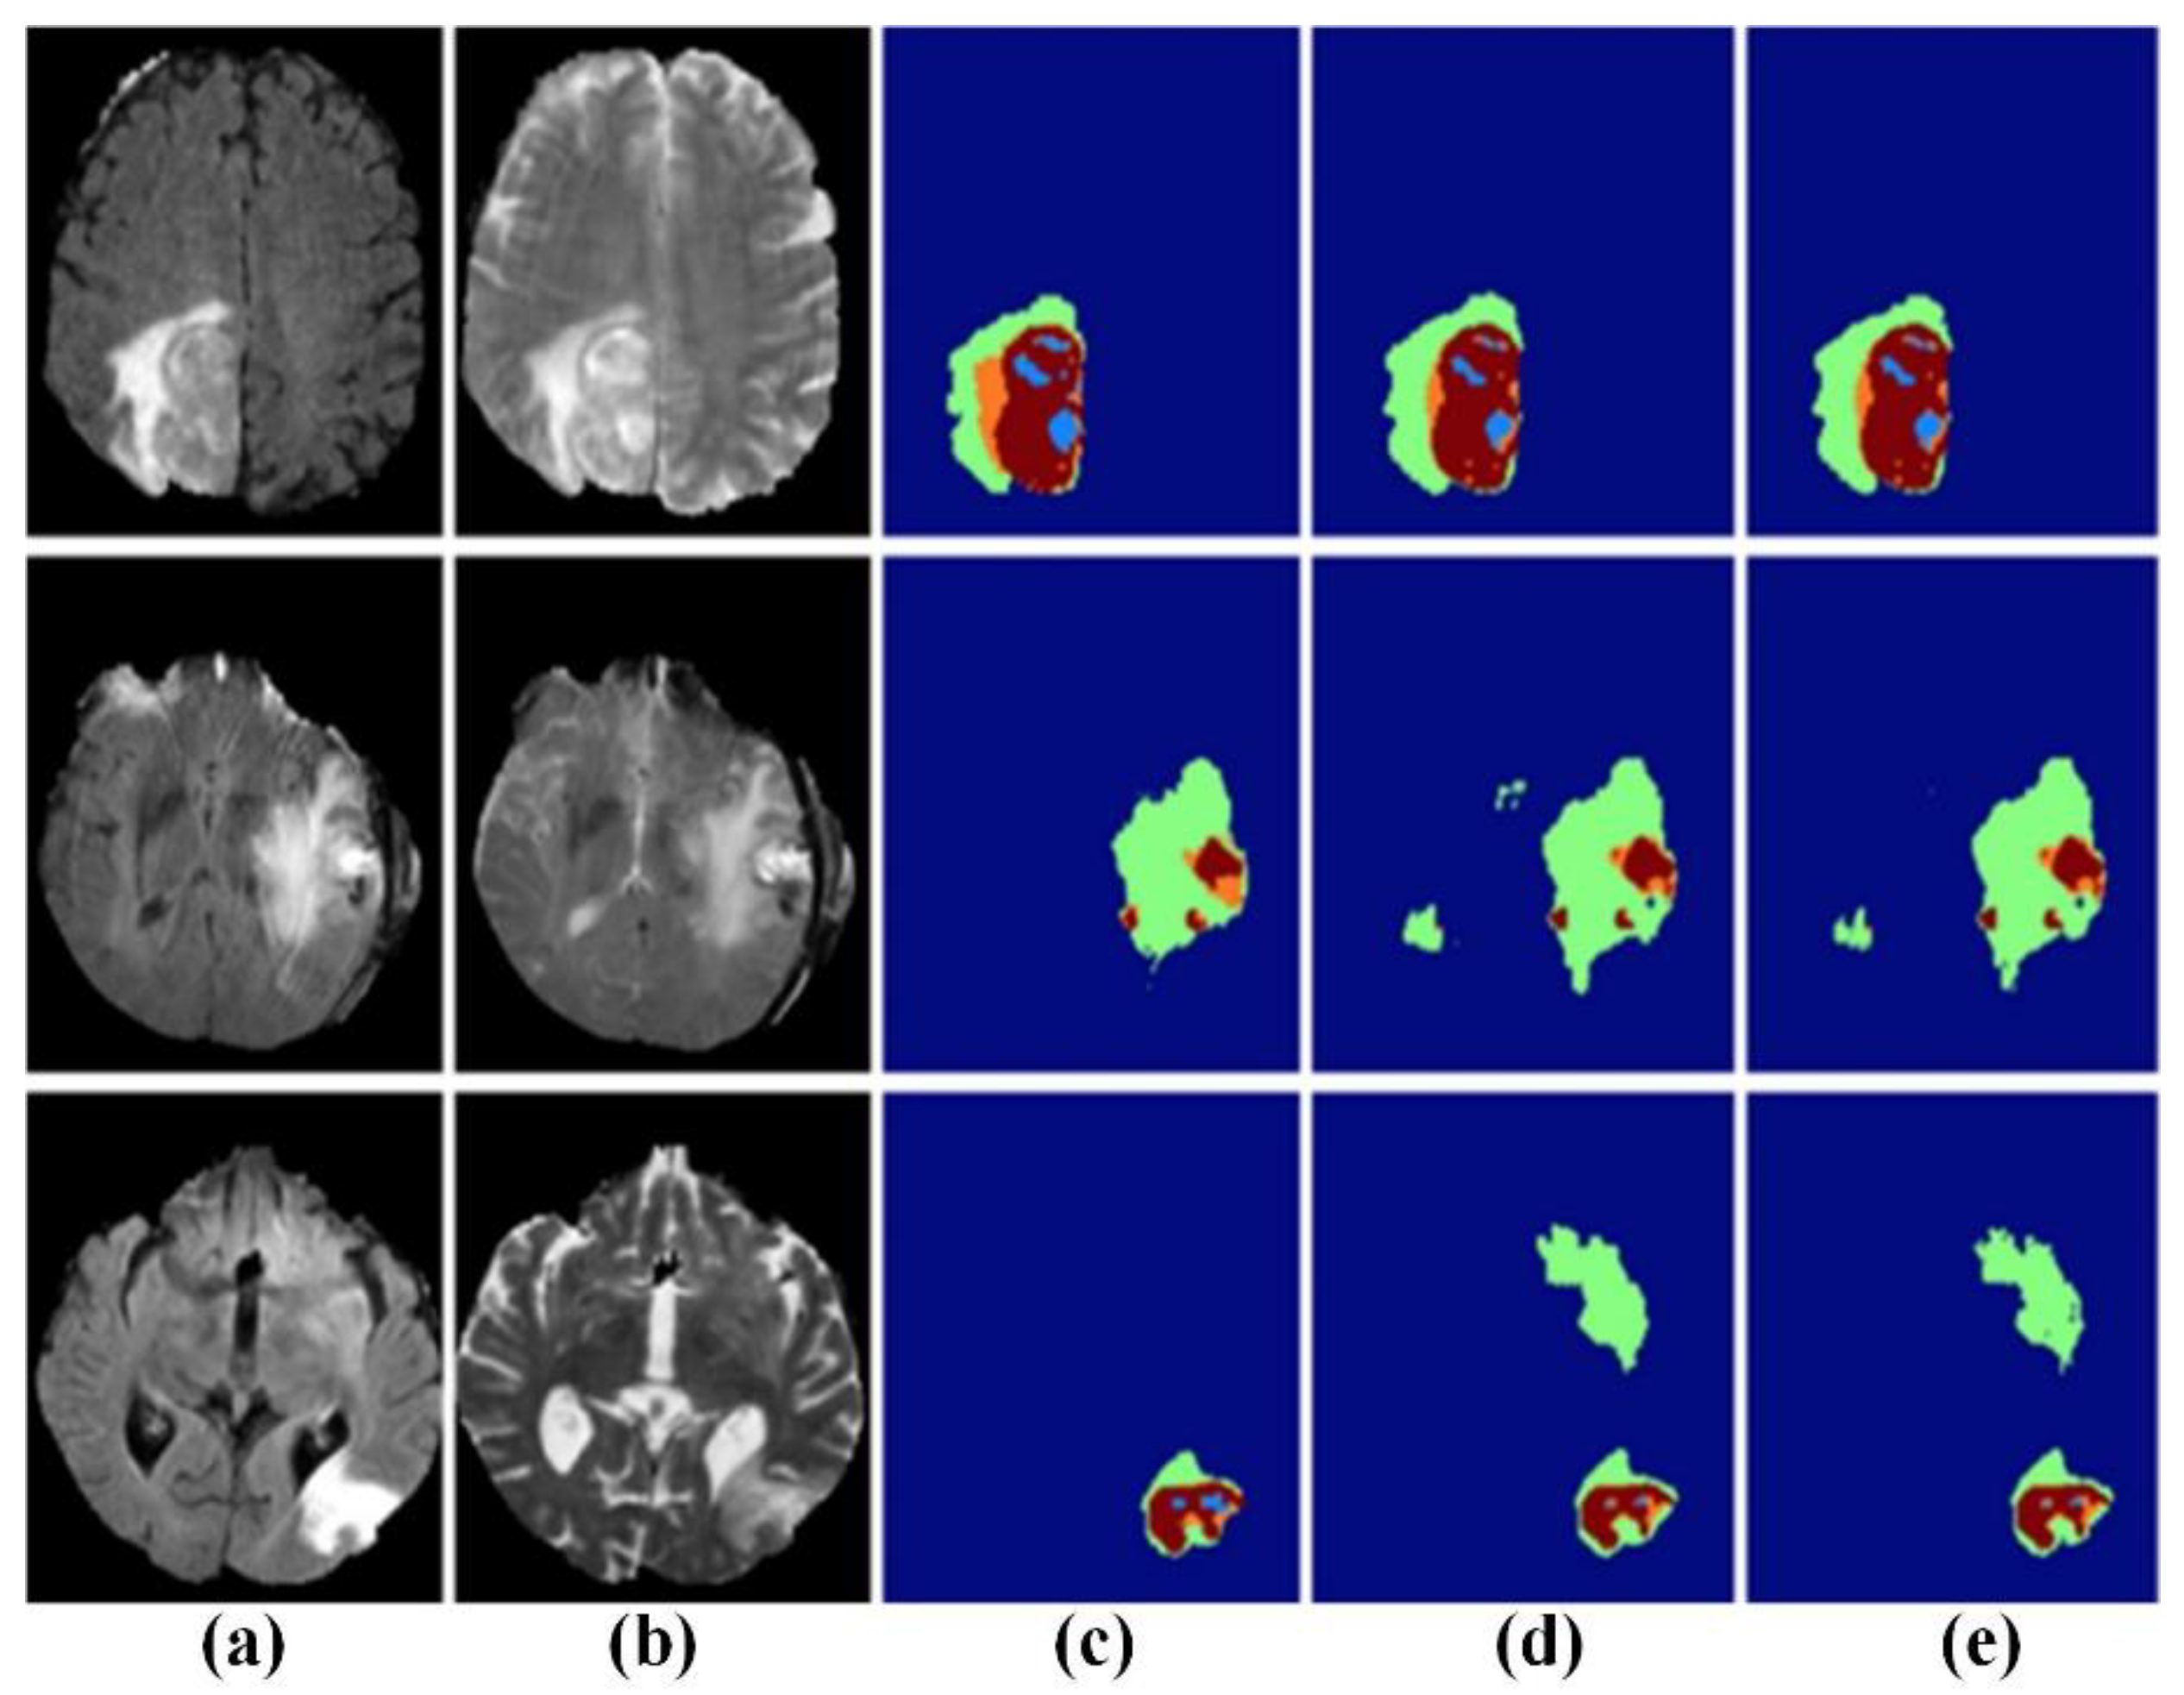

4.3. Application of Machine Learning in MRI Brain Tumor Segmentation Image